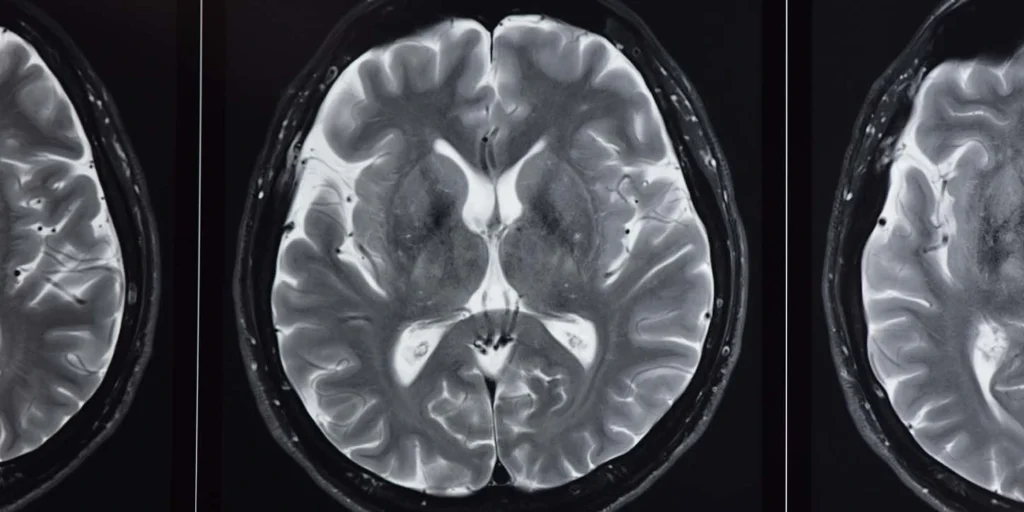

- Ressonância magnética (RM): pode mostrar sinais típicos como o “sinal da cruz” no tronco cerebral ou o “contorno brilhante do putâmen”.

No Brasil, a ressonância de crânio é o exame mais disponível e pode reforçar o diagnóstico.